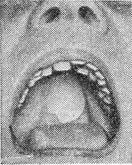

![]() Плаваючий обтуратор неба.  |

Просвіти при уроджених ущелинах піднебіння заповнюють так званим плаваючим, тобто рухомим, О. (рис. 1) - тонкою пластинкою, потовщені краї якої седлообразно захоплюють краю твердого піднебіння, а задня частина утримується кільцем скорочувальних м'язів м'якого піднебіння і задньої стінки глотки. Задня частина плаваючого обтуратора повинна бути сформована у відповідності з положенням і рухами м'язів м'якого піднебіння і задньої стінки глотки. Доцільно застосувати плаваючий О. до прорізування зубів (вже в перші дні після народження) (рис. 2). Це оберігає дітей від запальних ускладнень у дихальних шляхах, слухових трубах і середньому вусі і створює майже нормальні умови для розвитку правильної вимови.

Рис. 2. Плаваючий обтуратор для дитини до прорізування зубів (на гіпсовій моделі).